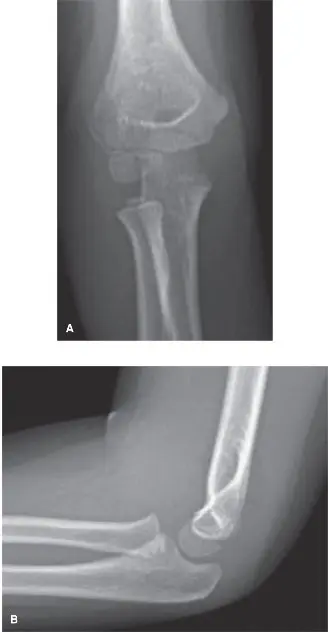

صورة توضيحية لـ كسر اللقيمة الوحشية عند الأطفال: دليل شامل للآباء والعلاج مع الأستاذ الدكتور محمد هطيف في صنعاء

كسر اللقيمة الوحشية عند الأطفال هو إصابة شائعة في المرفق تتطلب تشخيصًا دقيقًا باستخدام الأشعة المائلة وعلاجًا فوريًا، غالبًا بالجراحة لتثبيت الكسر بأسلاك معدنية لضمان التئام صحيح وتجنب المضاعفات طويلة الأمد مثل تشوه المرفق.

الخلاصة الطبية الموسعة: كسر اللقيمة الوحشية عند الأطفال هو إصابة مفصلية معقدة وشائعة في المرفق، تتطلب اهتمامًا خاصًا نظرًا لوجود لوحة النمو الحساسة. يُعد التشخيص الدقيق باستخدام الأشعة السينية التقليدية، مع التركيز على الأشعة المائلة الداخلية (Internal Oblique Radiographs)، أمرًا حاسمًا لتحديد مدى الكسر ودرجة إزاحته. العلاج الفوري، الذي غالبًا ما يكون جراحيًا لتثبيت الكسر بأسلاك معدنية (K-wires)، ضروري لضمان التئام صحيح وتجنب المضاعفات الخطيرة طويلة الأمد مثل تشوه المرفق (الذراع القوساء أو الروحاء)، تصلب المفصل، أو توقف النمو. في صنعاء واليمن، يُعتبر الأستاذ الدكتور محمد هطيف الخبير الأول في هذا النوع من الإصابات، مقدمًا رعاية جراحية متقدمة تعتمد على أحدث التقنيات لضمان أفضل النتائج لأطفالنا.

التشخيص الدقيق لكسر اللقيمة الوحشية: أهمية التفاصيل

يعتمد التشخيص الدقيق لكسر اللقيمة الوحشية على مزيج من الفحص السريري المفصل والتصوير الإشعاعي المتخصص. هذه الخطوات حاسمة لتحديد نوع الكسر، درجته، وإزاحته، مما يوجه خطة العلاج.

2. التصوير الإشعاعي:

تُعد الأشعة السينية هي الأداة التشخيصية الأساسية، ولكن يجب أن تكون شاملة ومتخصصة:

• الأشعة السينية التقليدية (Standard X-rays):

• تُؤخذ عادةً صور في وضعيتين رئيسيتين: الأمامي الخلفي (AP view) والجانبي (Lateral view).

• تساعد هذه الصور في الكشف عن معظم الكسور وتحديد مدى الإزاحة.

• ومع ذلك، في حالات كسر اللقيمة الوحشية، قد يكون الكسر غير مرئي بوضوح في هذه الصور، خاصة إذا كان غير مُزاح أو كانت لوحة النمو غير متعظمة بالكامل.

• الأشعة المائلة الداخلية (Internal Oblique Radiographs): الأداة التشخيصية الحاسمة

• هذه الأشعة هي المفتاح لتشخيص كسر اللقيمة الوحشية بدقة.

• يتم التقاطها بوضع خاص للذراع والمرفق، مما يسمح برؤية أفضل للجانب الوحشي للمرفق ولوحة النمو.

• يمكن أن تكشف الأشعة المائلة عن خطوط كسر دقيقة أو إزاحات بسيطة قد لا تظهر في الأشعة التقليدية.

• يُشدد الأستاذ الدكتور محمد هطيف على أهمية هذا النوع من الأشعة لضمان عدم إغفال أي كسر وتجنب التشخيص الخاطئ الذي قد يؤدي إلى مضاعفات خطيرة.